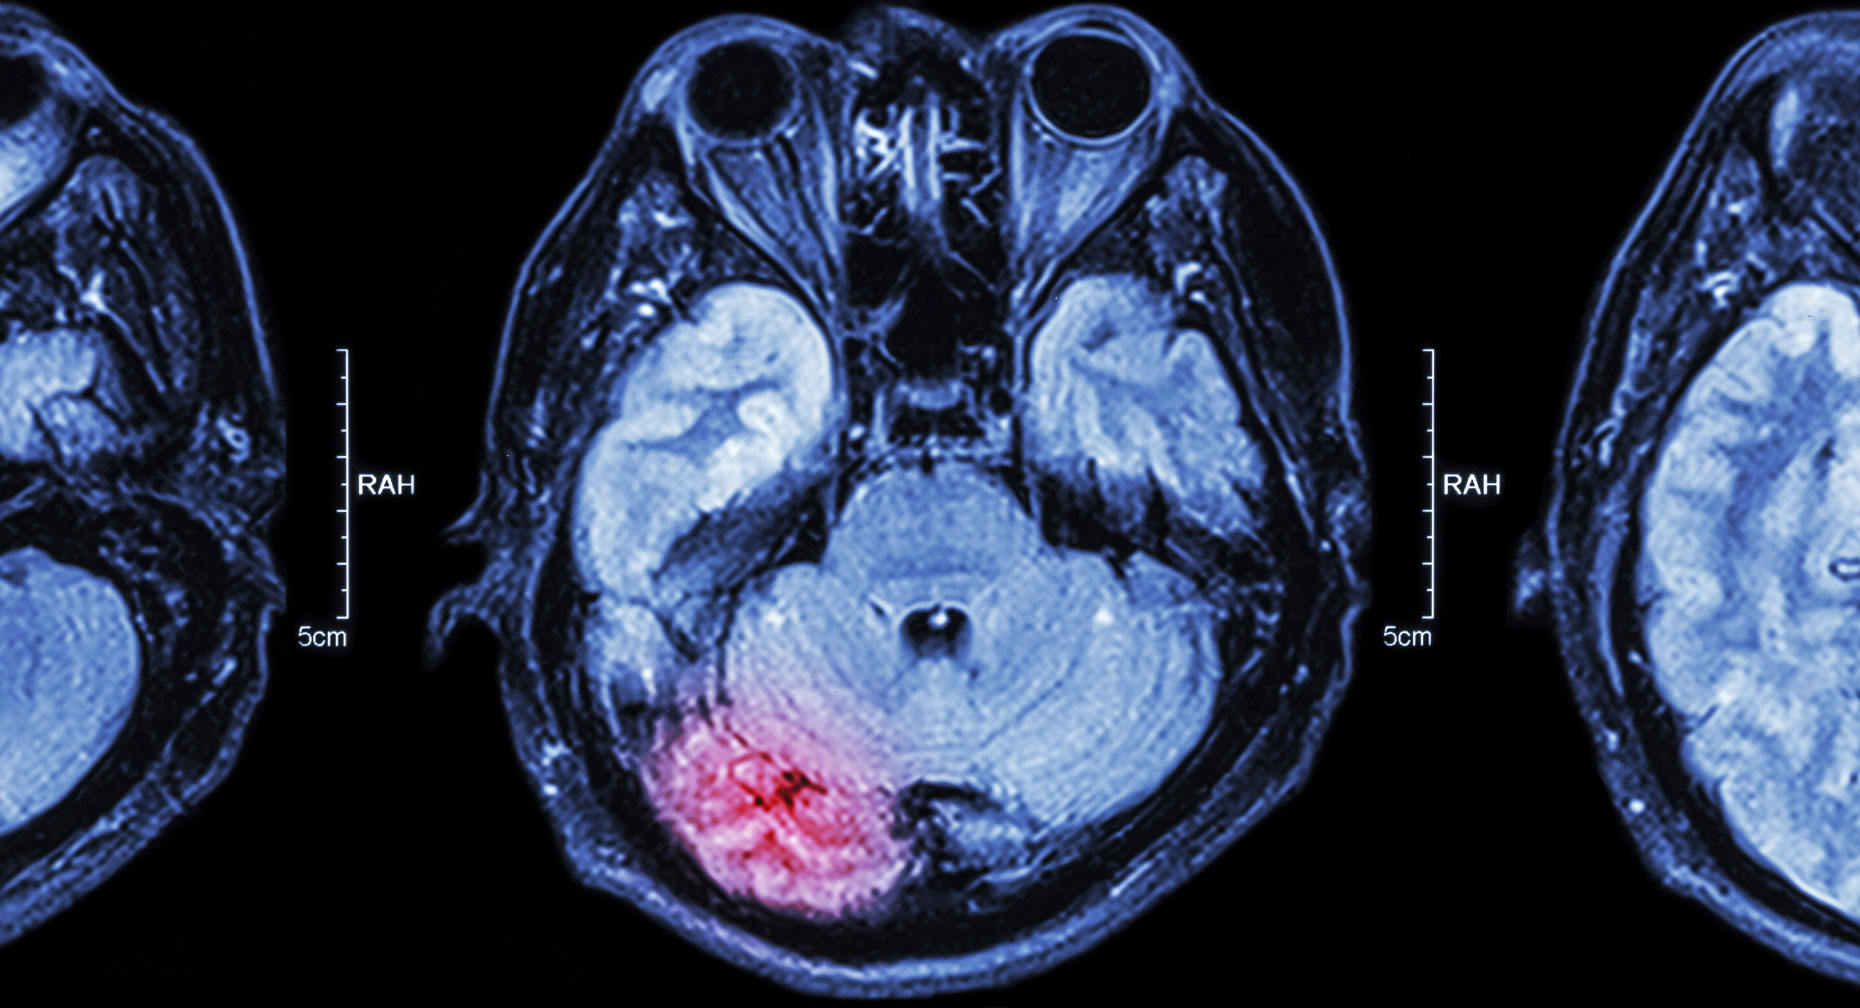

A stroke is loss of blood flow to part of the brain. It happens when a blood clot blocks an artery in the brain or when a bleed from a blood vessel in the head creates pressure in the brain.

Hemorrhagic stroke. When a blood vessel in the brain breaks or leaks due to weakness in the vessel wall, blood flows into or around the brain and creates swelling and pressure. This bleeding (or hemorrhage) damages brain cells and tissue.

Strokes from bleeding make up about 13 percent of all strokes, says the American Stroke Association, but they are the most deadly, causing about 40 percent of stroke deaths.